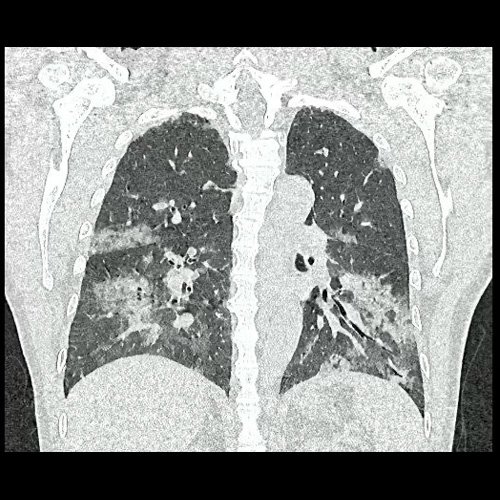

- Tomografía de tórax sin contraste endovenoso (Dia 0):Se observan múltiples áreas de consolidación parenquimatosa con broncograma aéreo y de distribución difusa por ambos pulmones, predominando en los lóbulos inferiores, asociadas a engrosamiento de los septos y rodeadas de tenue vidrio esmerilado. Se identifican estructuras ganglionares lateroaórticas, pretraqueales y subcarinales, ninguna de ellas sin alcanzar rango megálico.

Tomografia de torax sin contraste endovenosos (Ventana pulmonar- Corte coronal)

Tomografia de torax sin contraste endovenosos (Ventana pulmonar- Corte coronal)

Tomografia de torax sin contraste endovenosos (Ventana pulmonar- Corte coronal)

Tomografia de torax sin contraste endovenosos (Ventana pulmonar- Corte coronal)